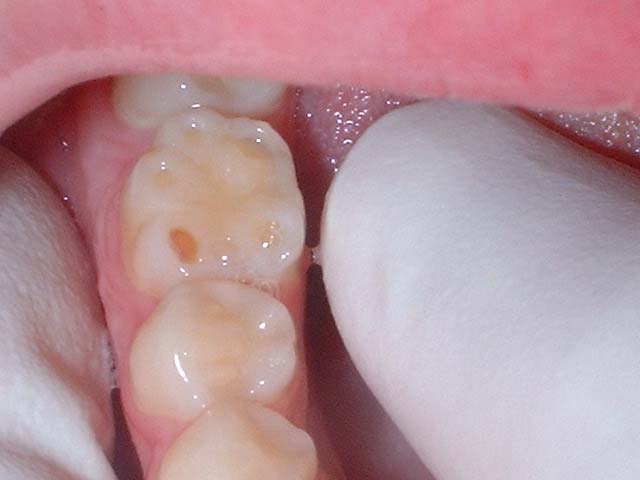

When a child is being examined assess the molars. As each cusp erodes a circle will appear on the cusp tip. If one circle is present less erosion has taken place than if the maximum number of five circles has taken place. Hence the name.

5 Circles (Three buccal, two lingual cusps eroded – LR6)